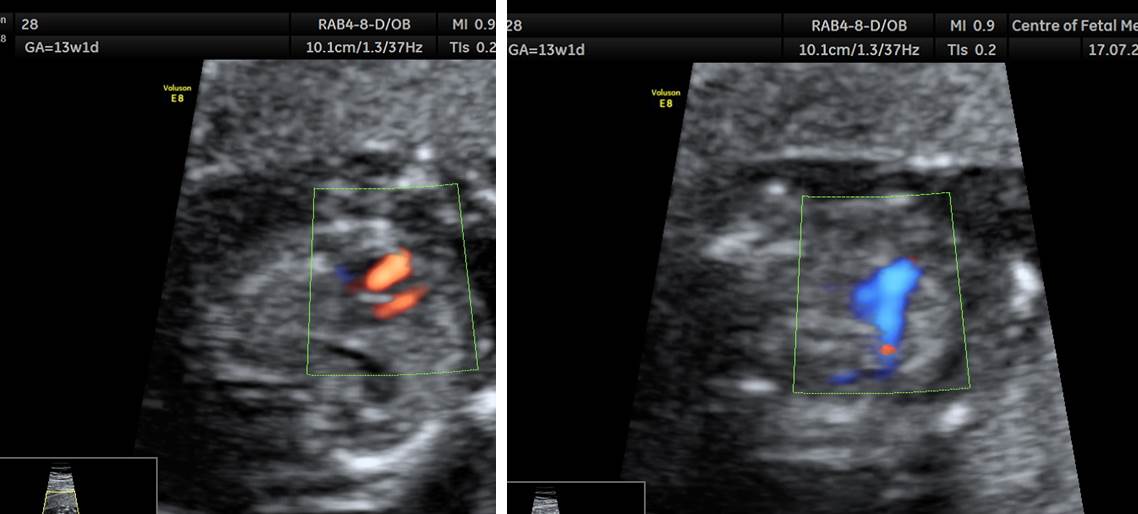

Вопрос 3

Какая оптимальная скорость цветовового Допплера для оценки легочных вен?

• А — 15-20 см/сек​

• Б — 30-40 см/сек​

• В — более 40 см/сек

Ответ на вопрос 3

Вопрос 4

Какая оптимальная скорость цветовового Допплера для оценки магистральных сосудов сердца?

• Б — 20-30 см/сек

• В — 35-45 см/сек​

Ответ на вопрос 4